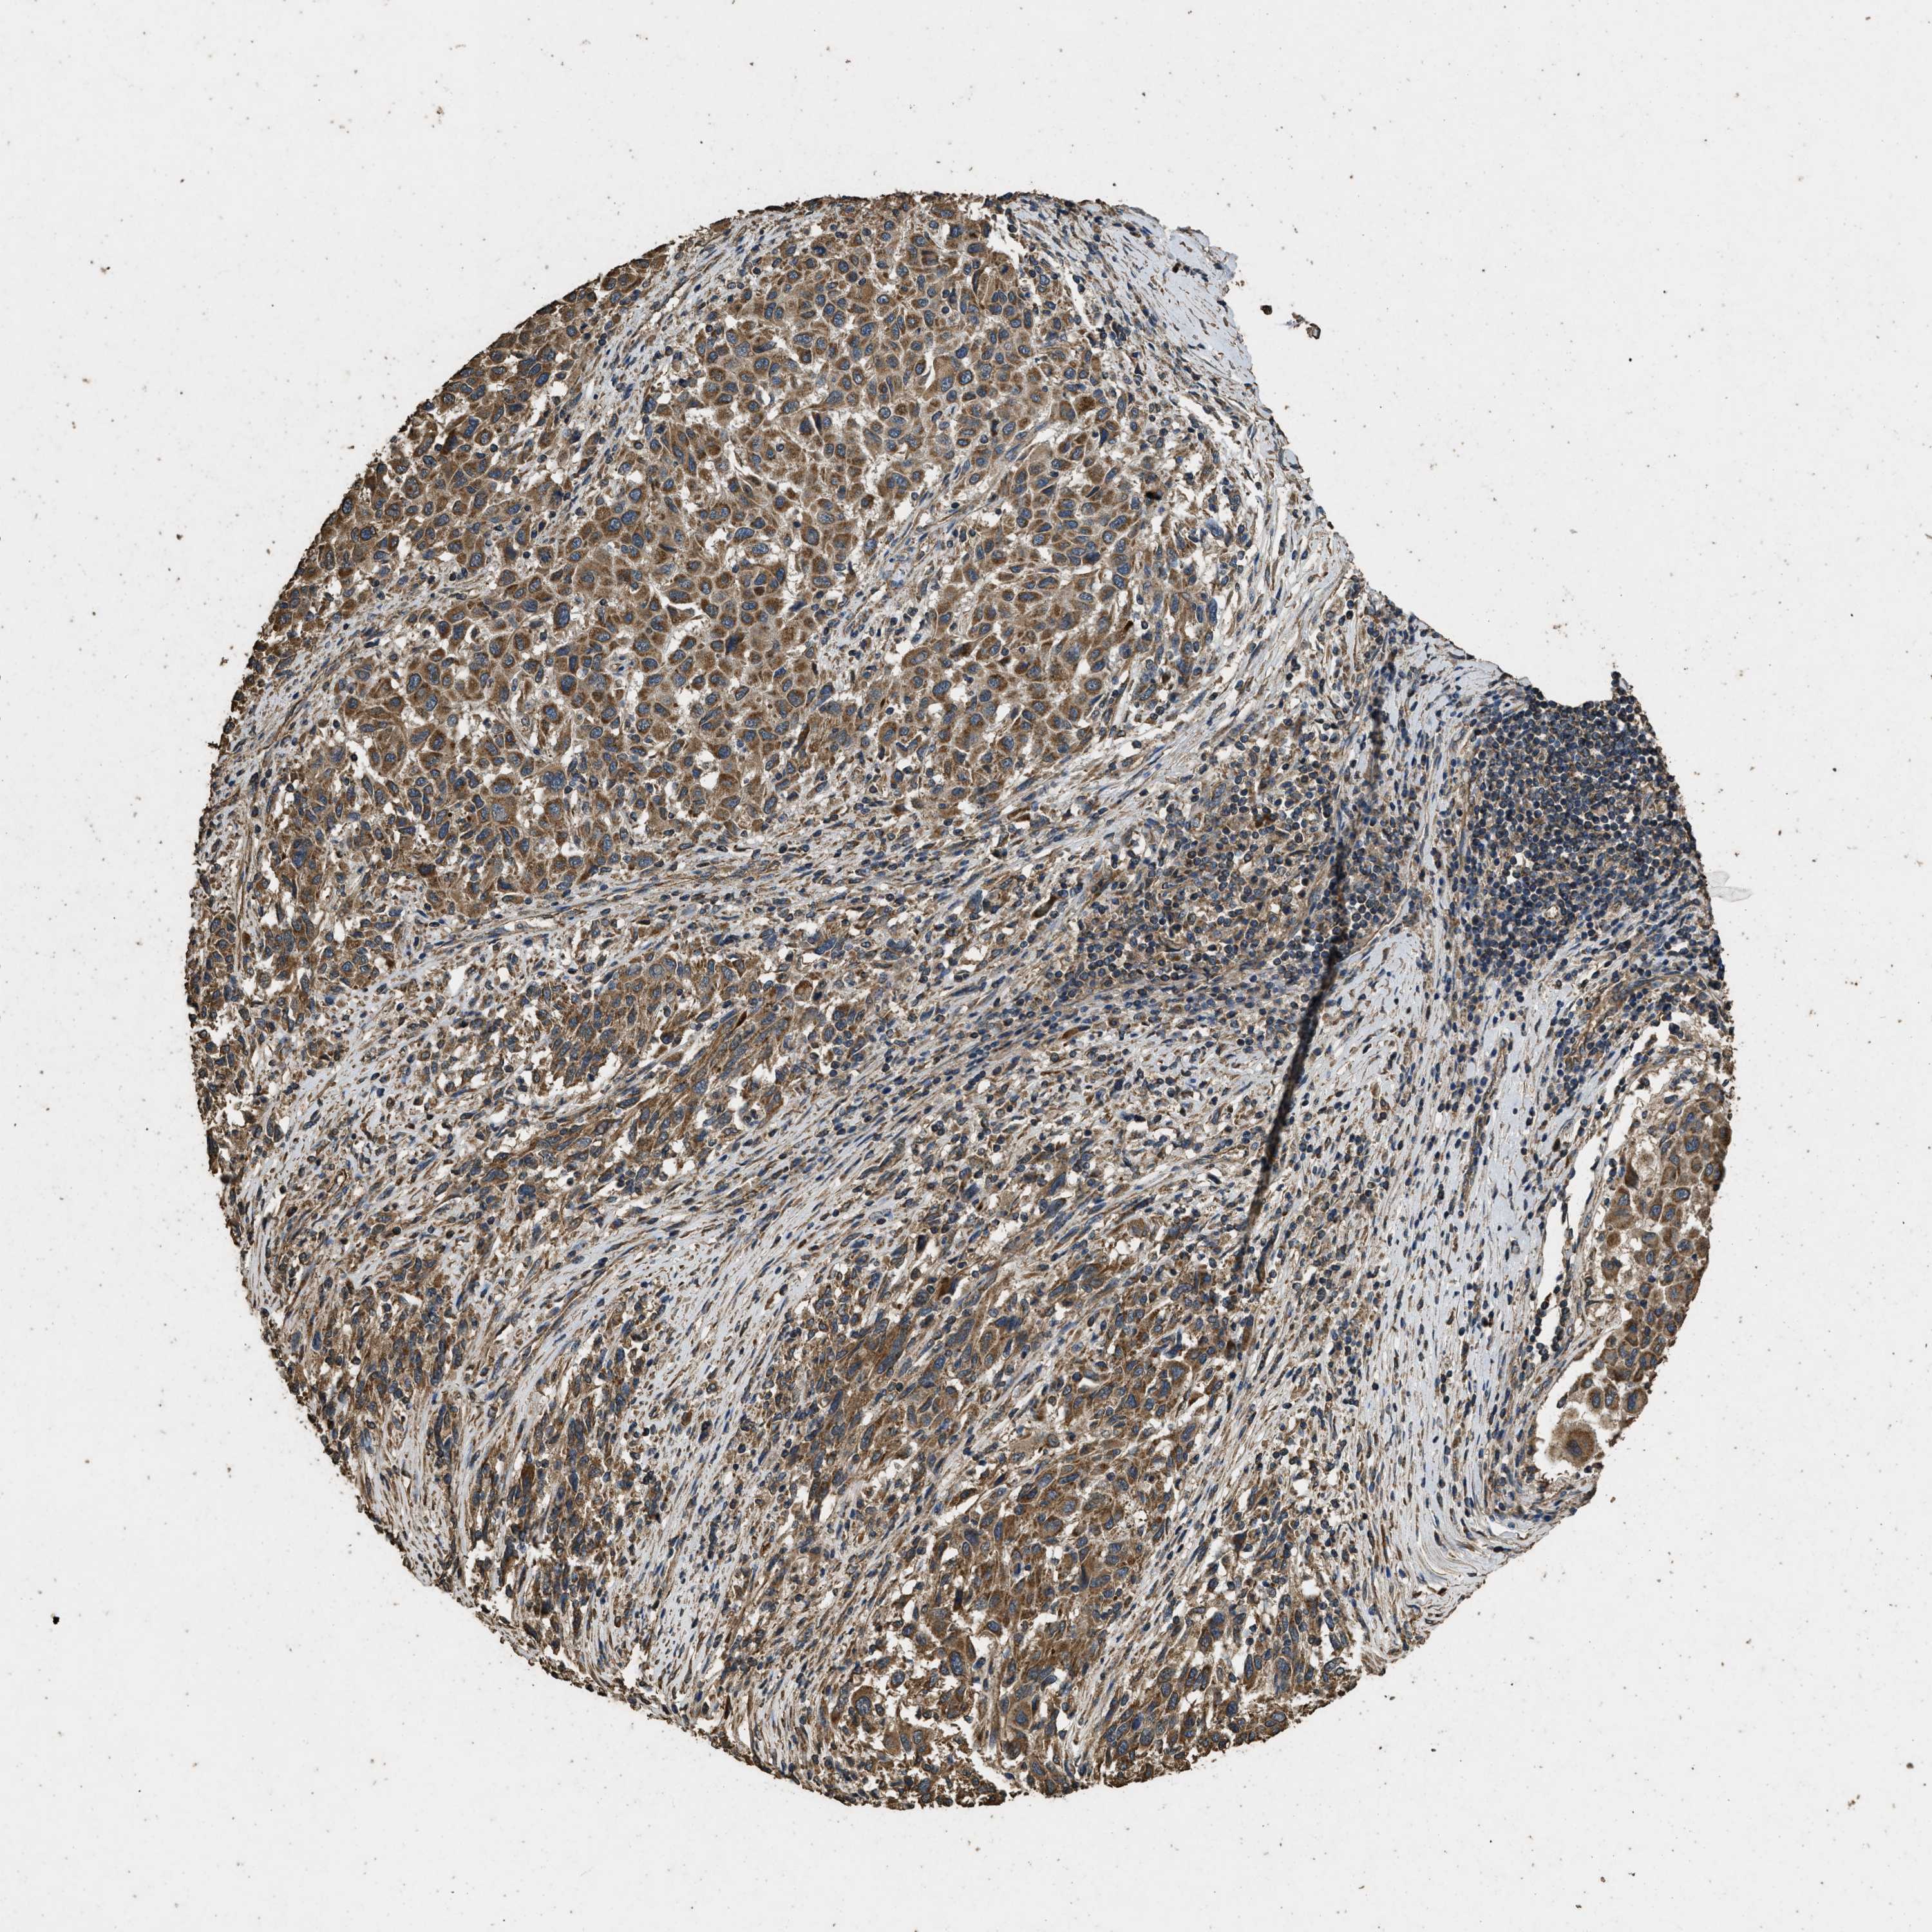

MELANOMA - Protein expressioni

A mouse-over function shows sample information and annotation data. Click on an image to view it in a full screen mode. Samples can be filtered based on level of antibody staining by selecting one or several of the following categories: high, medium, low and not detected. The assay and annotation is described here.

Note that samples used for immunohistochemistry by the Human Protein Atlas do not correspond to samples in the TCGA dataset.

Antibody stainingi

Antibody staining in the annotated cell types in the current human tissue is reported as not detected, low, medium, or high, based on conventional immunohistochemistry profiling in selected tissues. This score is based on the combination of the staining intensity and fraction of stained cells.

Each image is clickable and will lead to virtual microscopy that enables deeper exploration of all samples and also displays staining intensity scores, fraction scores and subcellular localization as well as patient and tissue information for each sample.

Antibody CAB017847

Staining

High

Medium

Low

Not detected

Intensity

Strong

Moderate

Weak

Negative

Quantity

>75%

75%-25%

<25%

None

Location

Nuclear

Cytoplasmic/membranous

Cytoplasmic/membranous,nuclear

Malignant melanoma, NOS

Malignant melanoma, Metastatic site